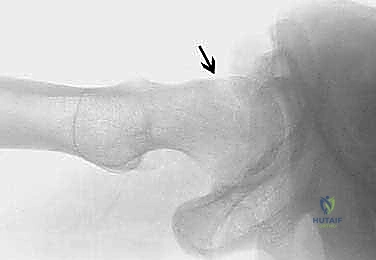

يحدث هذا النوع عندما لا يكون رأس عظم الفخذ كروياً بشكل مثالي. بدلاً من ذلك، تتكون نتوءات عظمية إضافية عند منطقة التقاء رأس وعنق الفخذ. هذا الشكل غير الدائري يجعله يحتك بقوة بحافة التجويف (الحُق) أثناء الحركة، مما يؤدي إلى "كشط" وتمزيق الغضروف والشفا الحقي. هذا النوع شائع جداً بين الشباب والرياضيين الذكور.

- الأشعة السينية (X-rays): لتقييم شكل العظام، قياس "زاوية ألفا" (Alpha Angle)، وتحديد وجود نتوءات الكامة أو الكماشة.

* إذا كان الانحشار من نوع "الكامة"، يتم نحت عنق عظم الفخذ ليعود لشكله الانسيابي.